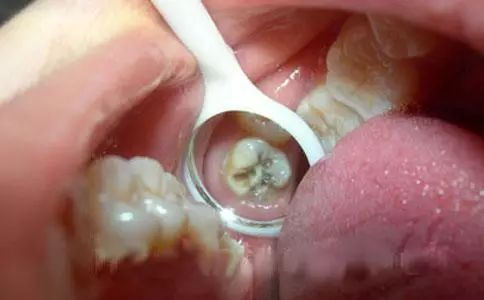

通常嚟講,牙醫唔會輕易拔牙嘅!即使你牙齒痛得非常厲害,都要睇下你蛀牙嘅程度!一般嚟講,輕度蛀牙無傷到牙神經,牙醫會用樹脂填充來補牙。如果要抽牙神經,咁就係話明你嚴重蛀牙,需要進行根管治療同埋戴個牙套保護。

如果你有輕微蛀牙,一般樹脂材料補牙大約幾百元嘅費用;